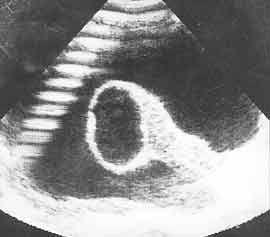

Рис. 7. Стафилококковый менингит. Склерозированная киста зрительного бугра после абсцесса.